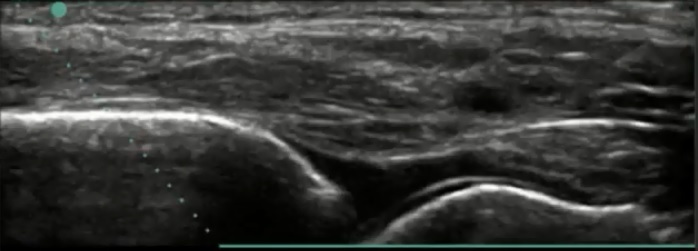

Bild 2: Fuß und Sprunggelenk, Erguss, Recessus anterior